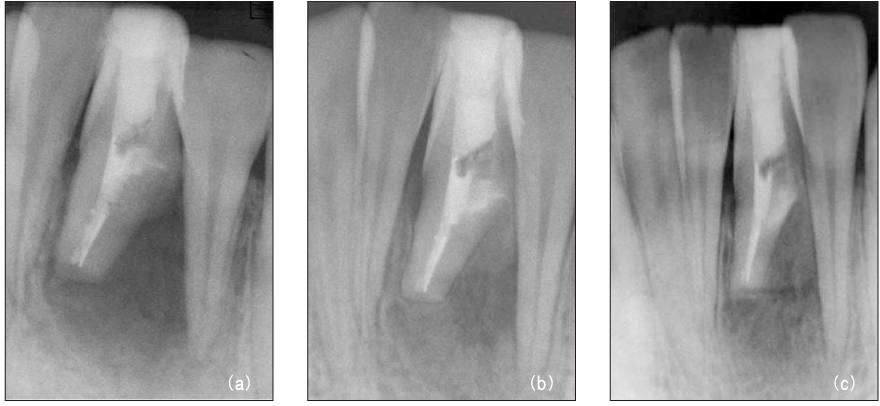

Figure 3

File separation in the root canal (a, b) and remove using ultrasonic device under microscope (c).

Figure 3 File separation in the root canal (a, b) and remove using ultrasonic device under microscope (c).